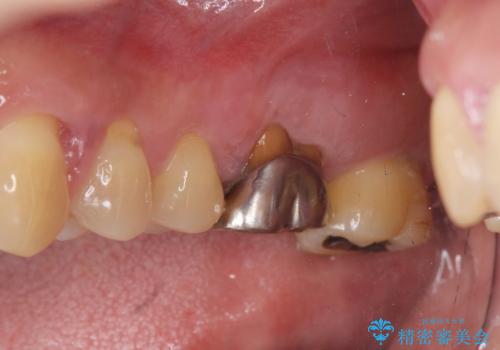

- 夜間のくいしばり、はぎしりが激しく全体的な歯周病が進行し、治療を希望され来院されました。

歯周ポケットの徹底的な除去を行なったのち、歯の揺れを抑え、過大な力がかからぬよう連結クラウン(歯周補綴)を行い強大な力に対抗します。